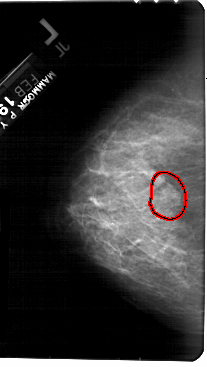

A_1397_1.RIGHT_MLO

FILE: A_1397_1.RIGHT_MLO.OVERLAY

TOTAL_ABNORMALITIES 1

ABNORMALITY 1

LESION_TYPE MASS SHAPE LOBULATED MARGINS OBSCURED

ASSESSMENT 4

SUBTLETY 3

PATHOLOGY BENIGN

TOTAL_OUTLINES 1

BOUNDARY